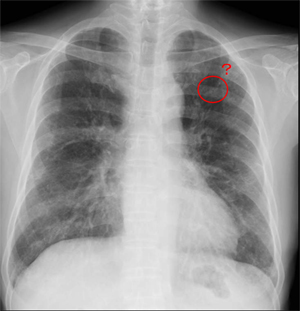

CXR PA

定期受診時(2010.05.10)Baseline

初診時(2010.05.19)

初診5日後 (2010.05.24)

(2010.06.11)背景肺に軽度の肺気腫+間質性肺炎像

(2010.07.18)縦隔リンパ節腫大